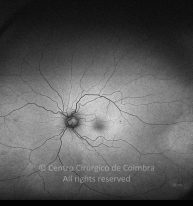

Traumatismo con un clavo en el ojo derecho hace unos 20 años, con perforación de la córnea y del iris. Catarata traumática. MAVC: 20/60 OD; OI ambliope.

Retinografía color

Cicatriz temporal. Antecedentes de vitrectomía con vítreo inferior no removido.